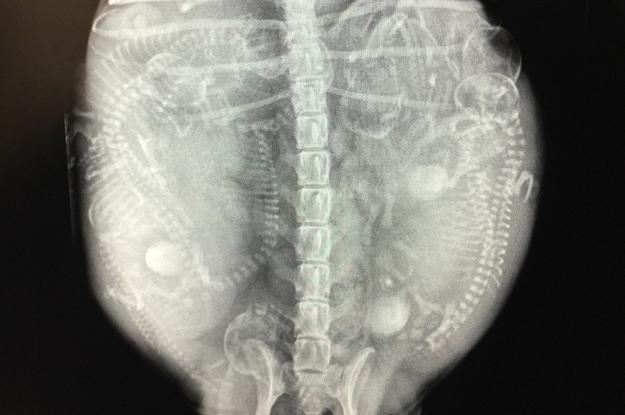

上記の理由から、分娩前には交配後55日でレントゲン検査を実施し、胎児の数や母体の骨盤の大きさを計測しておくことをおすすめします。

レントゲンでは

- 胎子の頭数

- 胎子の姿勢

- 胎子と母体の骨盤の大きさの比較

- 同腹胎子の成長の差

- 子宮内にガスがある

といったことを確認することができ、同腹胎子の成長の差や子宮内のガスは胎子が死亡している可能性を示しています。